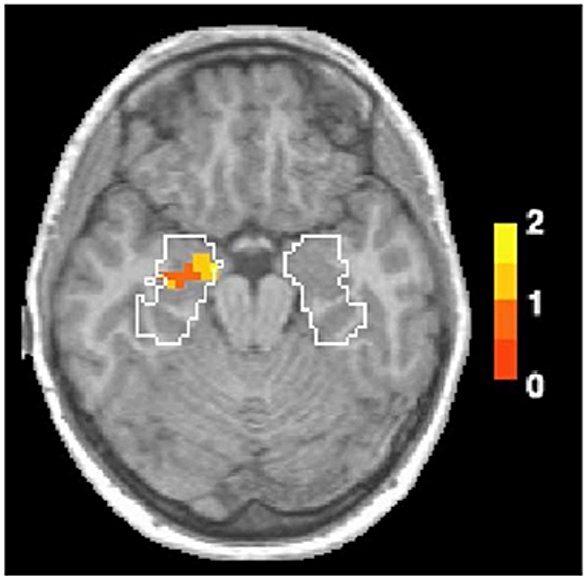

Koku bilgisi, buruna girip koku soğancığını geçtikten sonra amigdala ve hipokampusa gönderilir. Koku alma, beynin bu bölgesinde işlenen tek duyudur. Bu nedenle koku, beynin duygu, öğrenme ve hafızayla ilgili alanlarıyla en güçlü şekilde bağlantılı olan duyudur. FMRI taramaları (insanlar zihinsel görevleri yerine getirirken beyin aktivitesini ölçen bir teknik) sayesinde, artık taze kesilmiş çim kokusunun neden bizi anılarımızda geçen bir yaza götürdüğünü veya neden sadece bir hamur işi kokusundan çocukluğunu bu kadar net hatırladığını açıklayan kanıtlarımız var. Çim veya hamur işi koklamak, beynin duygulardan ve anılardan sorumlu bölgelerini harekete geçirir![1]